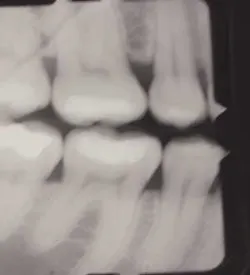

Early inter-proximal decay #12 (DIFOTI and X-ray)

Peers, et al in 1993 found that the sensitivity of fiber-optic transillumination in the discovery of dental caries exceeded that of radiographs. Early phases of tooth decay are currently difficult to detect. While radiographs can disclose established cavities, particularly those that occur between the teeth, they are not effective in detecting early decay. Vaarkamp and Veerdonschot demonstrated that early diagnosis of approximal carious lesions was feasible when light was propagated through the carious tissue.

Schneiderman, et. al. (Caries Research 1997) demonstrated that DIFOTI is two times more sensitive than bitewing radiographs for detection of interproximal tooth decay (X-ray 31 percent; DIFOTI 69 percent); four times more sensitive for occlusal decay (X-ray 20 percent; DIFOTI 80 percent); and 10 times more sensitive for smooth surface decay (X-ray 4 percent; DIFOTI 41 percent).